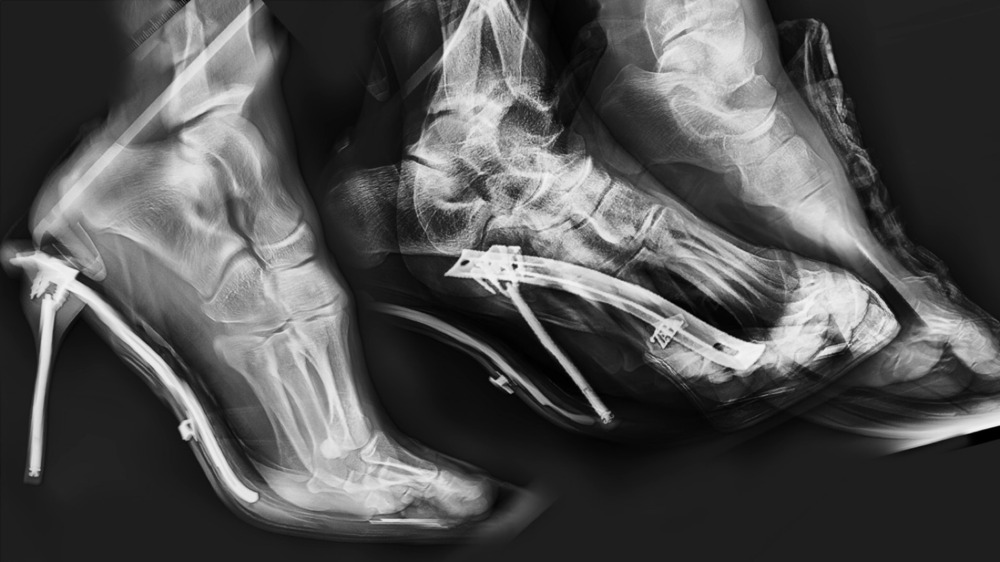

She later turned to the mechanical apparatuses that mediate bodily imagery — the camera, X-ray, and medical equipment. In 《Glove box》, these devices are re-positioned not as recording tools but as structures of control. Videos and objects in the space interweave perspectives of dissection, resuscitation, and observation, constructing a sensation in which the body can no longer remain a part of “me.” Particularly in Ray, desire is overlaid with X-ray images, dissolving the boundary between inside and outside, life and the inanimate.